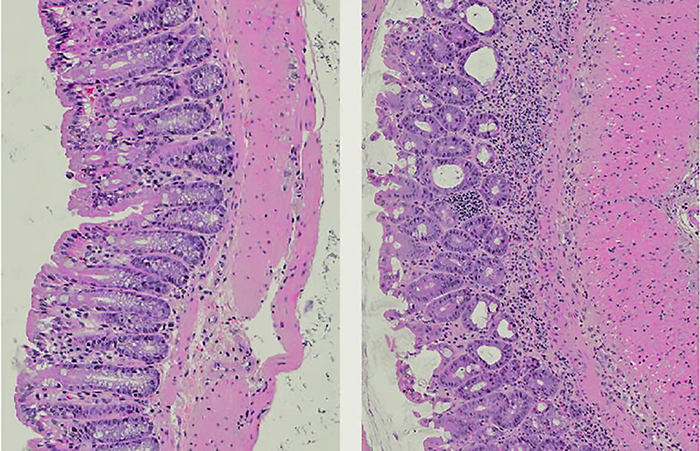

За счёт большого объёма данных удалось очень чётко установить корреляцию между изменениями на маммографии и вероятностью развития рака. Причём корреляцию удавалось установить даже на тех снимках, на которых рентгенологи-люди не видели никаких аномалий.

Срок прогнозирования составил 5 лет, кроме того, теперь куда более точный прогноз можно получить вне зависимости от расовой принадлежности, национальности и наследственности. Система анализирует именно состояние молочных желез по обычным маммографическим снимкам, и, как оказалось, этого вполне достаточно — информация о наследственности, принимаемых лекарствах, цвете кожи была статистически не значима и практически не повышала точности предсказания.